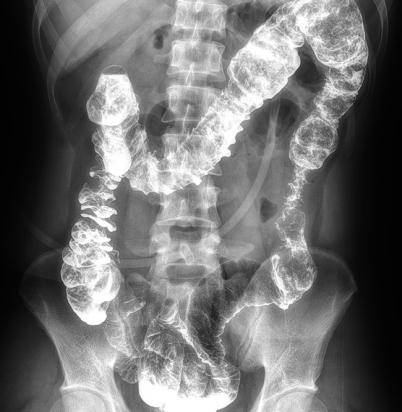

多功能動(dòng)態(tài)平板DR,采用U型臂結(jié)構(gòu),具有靜態(tài)DR攝影、數(shù)字透視、數(shù)字造影和可視化攝影的功能。

電動(dòng)旋轉(zhuǎn)內(nèi)平衡結(jié)構(gòu),可實(shí)現(xiàn)快捷擺位,滿(mǎn)足特殊體位的靜態(tài)與動(dòng)態(tài)檢查。